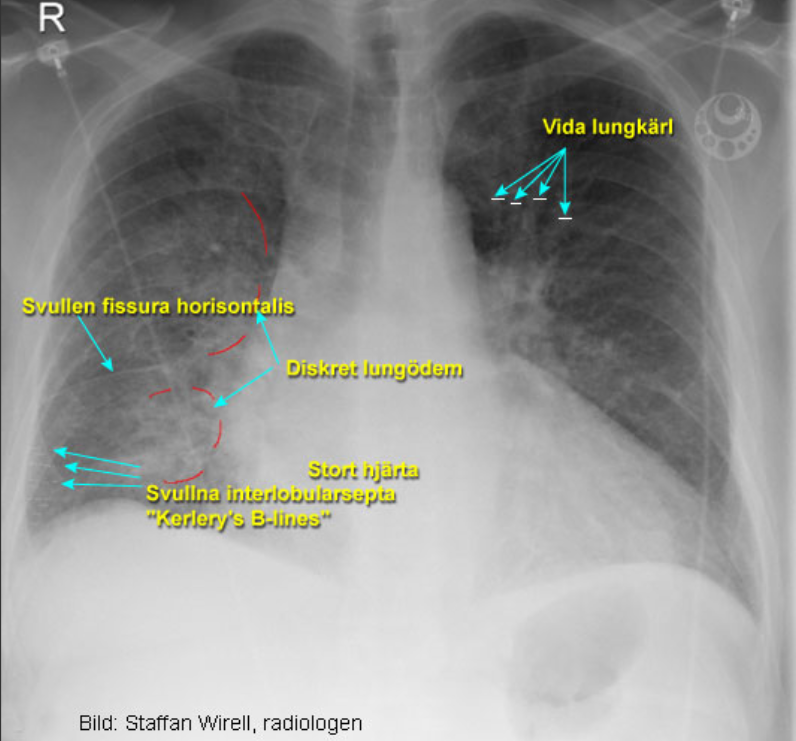

Vad visar bilderna?

Lungödem och normal lunga